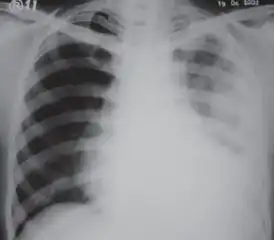

CXR of an individual affected by fibrothorax (consequence of tuberculosis)

Extensive left-sided fibrothorax

Chest radiograph displaying inhomogeneous opacification of the left half of the chest that is fibrothorax